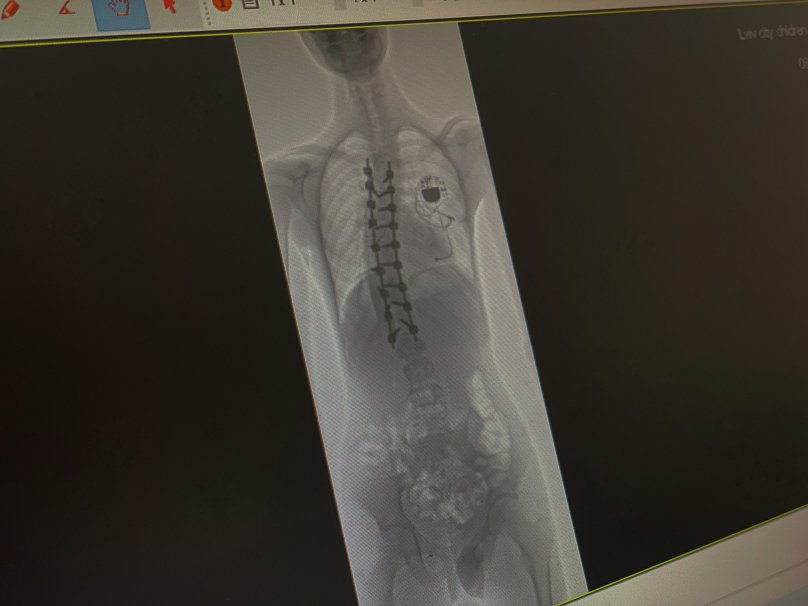

У дитячій лікарні Святого Миколая львівські медики разом з міжнародною командою на чолі з американським хірургом прооперували 16-річного підлітка зі сколіозом найважчого ступеня. Змалечку хлопець живе з кардіостимулятором, тож операцію з виправлення хребта було проводити ризиковано. Однак втручання пройшло успішно і викривлення хребта вдалося зменшити з критичних 80° до 25°. Про це повідомили у Першому ТМО 20 березня.

Операцію проводили у кілька етапів. Спершу лікарі обережно відокремили спинний мозок Ярослава від навколишніх тканин. За словами медиків, це був один із найнебезпечніших моментів. Далі встановили металеву конструкцію зі стрижнів і гвинтів, яка дозволила вирівняти хребет.

“У результаті викривлення вдалося зменшити з критичних 80° до 25° — це максимально можливий для безпеки спинного мозку показник. А завдяки ретельній підготовці вдалося уникнути кардіологічних ускладнень”, — додали медики.

Вже на другий день після операції Ярослав зміг сісти, а на третій — зробив перші кроки. Через тиждень юнака виписали додому. Попереду його чекає ще кілька місяців реабілітації.